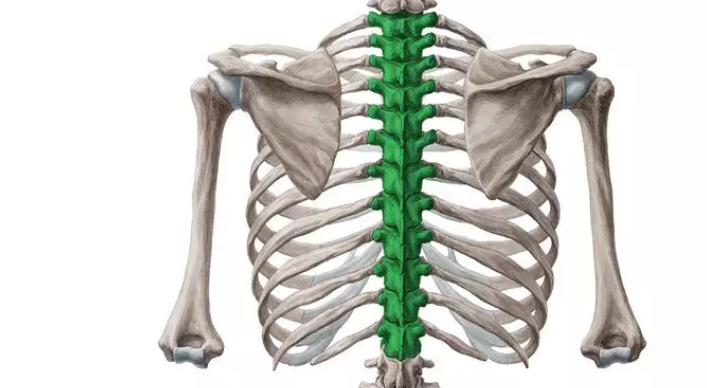

构成:幼年时椎骨共有33块(颈椎7块,胸椎12块,腰椎5块,骶椎5块,尾椎4块)。随年龄增长5块骶椎合成一块骶骨, 4块尾椎合成一块尾骨。

胸椎

整体结构:

前面观:椎体自上而下渐加宽,第2骶椎最宽

侧面观:可见颈、胸、腰、骶四个生理性弯曲,颈和腰曲凸向前,胸和骶曲凸向后。

颈椎前凸 20°- 40°,胸椎后凸 20°- 40°,腰椎前凸 30°- 50°,骶骨后凸倾斜。

后面观:颈椎棘突短而分叉,近水平位。胸椎棘突细长,斜后下方。腰椎棘突呈板状水平向后。